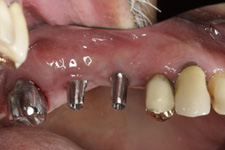

• Zavedení implantátu do kosti čelisti

• Zahojení do kosti – 3-4měsíce(v některých případech i déle – doplňování kosti)

Zavedení implantátů do kosti je většinou ambulantní chirurgický výkon, srovnatelný s vytržením zubu a většinou se provádí v lokální anestézii. Ve výjimečných případech je možné použít i analgosedaci či celkovou narkózu. Operaci provádí zubní lékař-implantolog při dodržení všech podmínek sterility pro operaci. Nástroje pro tuto operaci jsou konstruovány tak, aby výkon byl šetrný vůči kosti a zavedení implantátu bylo provedeno ve velmi krátké době. Díky kvalitní anestézii je výkon nebolestivý. Aby byl pooperační otok co nejmenší, je potřeba operovanou oblast chladit, dle poučení ošetřujícího lékaře. Lékař také ordinuje podle potřeby léky na bolest, případně antibiotika.